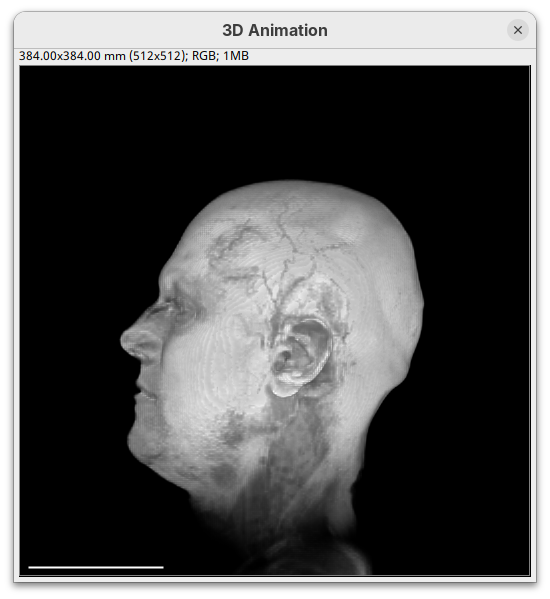

Two new windows will open: 3D Animation with the initial rendering of the data and Interactive Raycaster with all the fields to control the rendering parameters.

Note that this improves the visualization as the head’s surface becomes better visible.

The surface will become even more solid because we are defining that pixels that have a value above 250 will be fully opaque.

You will notice that the sample will become more transparent. Even the brain inside the skull will be visible.

The transformation menu has controls for rotating, translating, and scaling the sample. We can either add values or manually interact with the 3D Animation window to reorient the sample. Let’s try the latter.

- Left-click on the head and move it around.